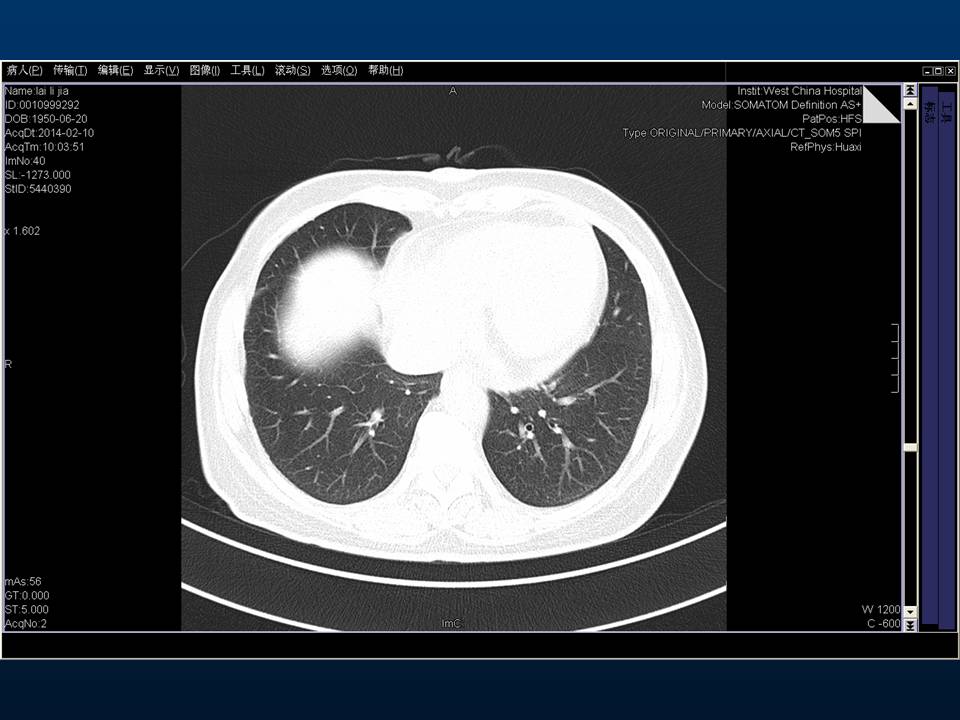

心房颤动(扑动)与“心衰”一例特殊病例报道